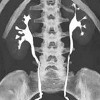

КТ мочевыделительной системы

Компьютерная томография мочевыделительной системы. Послойное сканирование почек и мочевыводящих путей рентгеновским методом с компьютерной обработкой полученных томографических срезов. КТ-урография может быть выполнена нативно (без контраста) и с внутривенным контрастным введением. Область сканирования включает область, которая включает почки, артерии и почечные вены, мочеточники и мочевой пузырь. Из срезов, полученных в ходе обследования, можно получить четкую картину морфологических характеристик мочевыводящих путей (расположение, размеры, структура органов) и плотности ткани. С помощью компьютерной томографии мочевыделительной системы можно диагностировать структурные нарушения, камни, новообразования и метастазы, кисты и абсцессы почек, уретерогидронефроз и другие патологии.